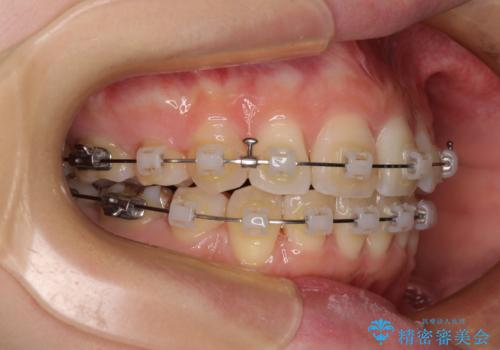

- 奥歯の欠損と、抜歯矯正の後戻りを気にして来院された患者様です。

上下前歯をワイヤー保定していましたが、強い舌の突出癖により上下ともにスペースができ、上下前歯は非接触になっていました。

マウスピース矯正でもワイヤー矯正後でも対応可能でしたが、自己管理の煩わしさからワイヤー矯正後を選択されました。

舌のトレーニングをしっかりと行っていただきながらワイヤー装置により矯正治療を行い、途中でインプラントを埋入し、矯正治療後に補綴治療を行うこととしました。